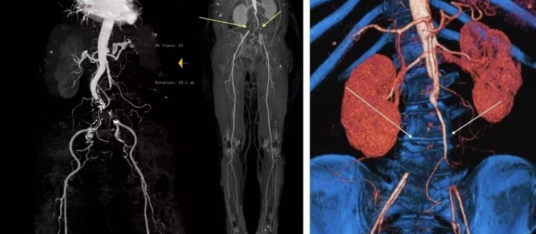

Leriche综合症又称主髂动脉闭塞性疾病(aortoiliac occlusive disease,AIOD)是指由腹主动脉下段或双侧髂动脉闭塞造成下肢和盆腔缺血;最早由法国医师Leriche对其进行系统的临床研究,并因此以其名字命名。典型表现即所谓的Leriche三联症:下肢间跛或静息痛、男性患者阳痿或阴茎勃起困难、股动脉搏动减弱或消失。本病可能由于动脉硬化、动脉瘤、创伤、肿瘤或异物损害壁而形成血栓,主动脉缓慢闭塞,可能有机会建立侧枝循环,一般只引起下肢动脉血运不良。

术中因双侧股动脉穿刺均困难,手推造影提示双侧股动脉闭塞。

遂果断另辟蹊径,经肱动脉穿刺成功,行腹主动脉造影证实右侧髂总动脉闭塞,左侧髂总动脉极重度狭窄并串珠样改变,故经股动脉入路此路不通。

头颈部血管造影提示:患者为右侧颈内动脉极重度狭窄合并右侧大脑中动脉闭塞。